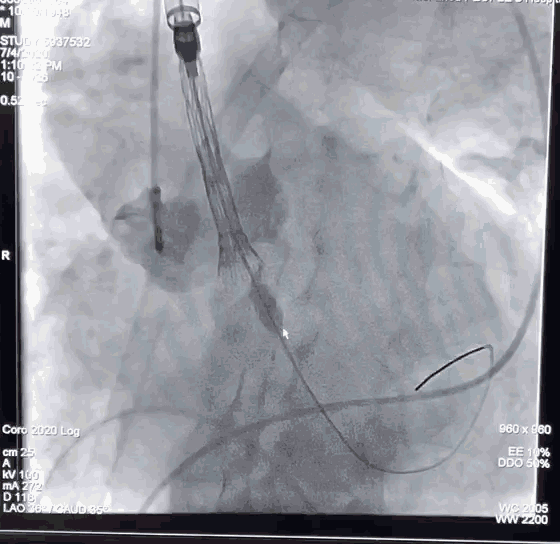

分离并切开右颈总动脉,植入大鞘建立通路

使用24mm球囊进行预扩张

由于患者的主动脉根部扭曲程度很大,猪尾导管无法置于无冠窦底,钟炜教授在释放时通过精准控制输送系统和适时造影,最终完美完成了瓣膜的释放。

主动脉根部扭曲程度大

猪尾很难到达主动脉根部,释放难度大

植入VitaFlow TAV 27的瓣膜,进行定位释放